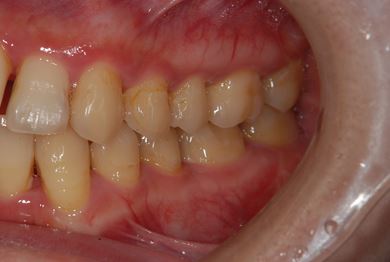

性別/年齢 女性 / 29歳

主訴 セラミック治療を希望。

治療方針 セラミック治療にて、審美的回復を行う。

治療内容 ハイブリッドセラミックインレー3本

治療部位

7 6 7

総治療費 113,715円

治療期間 2ヶ月

治療前